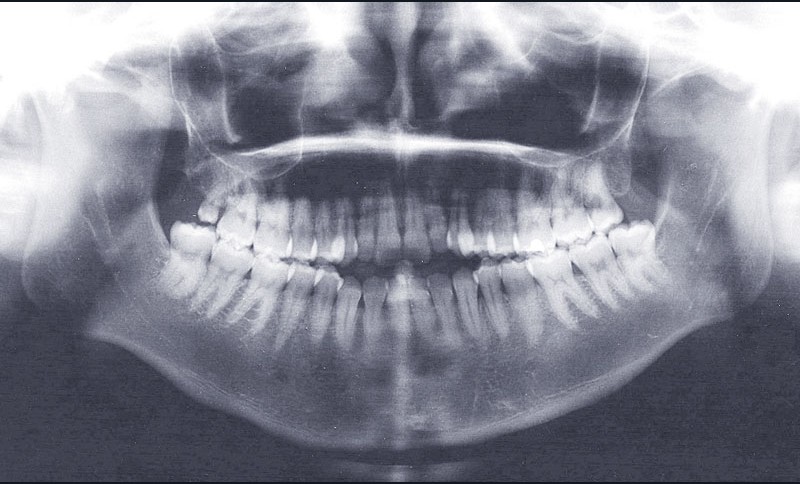

Diagnostic (fig. 1)

Cette patiente de 29 ans consulte pour des raisons principalement fonctionnelles mais également esthétiques. Elle présente :

– une classe II squelettique hyperdivergente

– une endognathie maxillaire

– une classe II division 1 majeure et asymétrique associée à une béance antérieure sévère

– un profil très convexe avec une occlusion labiale difficile et une biprochéilie

– une DDM par défaut modérée, maxillaire et mandibulaire

– des troubles de la posture et de la fonction linguale.